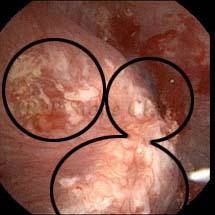

These images are taken as snap shots from the video recording of RIRS Surgery done at our hospital. These are Randall’s Plaques seen with Digital FLEX XC & Digital FLEX XC S. The cream or whitish patches are seen on the tips of RENAL PAPILLAE as seen in images below.

The Below Images Show Small Stones attached to the Renal Papillae.